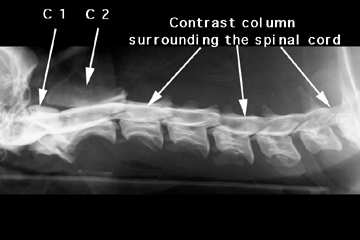

Myelography is performed by injecting contrast medium in to the subarachnoid space of the spinal column to confirm the presence and extent of a spinal cord lesion. Do you see the lesion? (Dorsal elevation of the C 4-5 ventral column.)